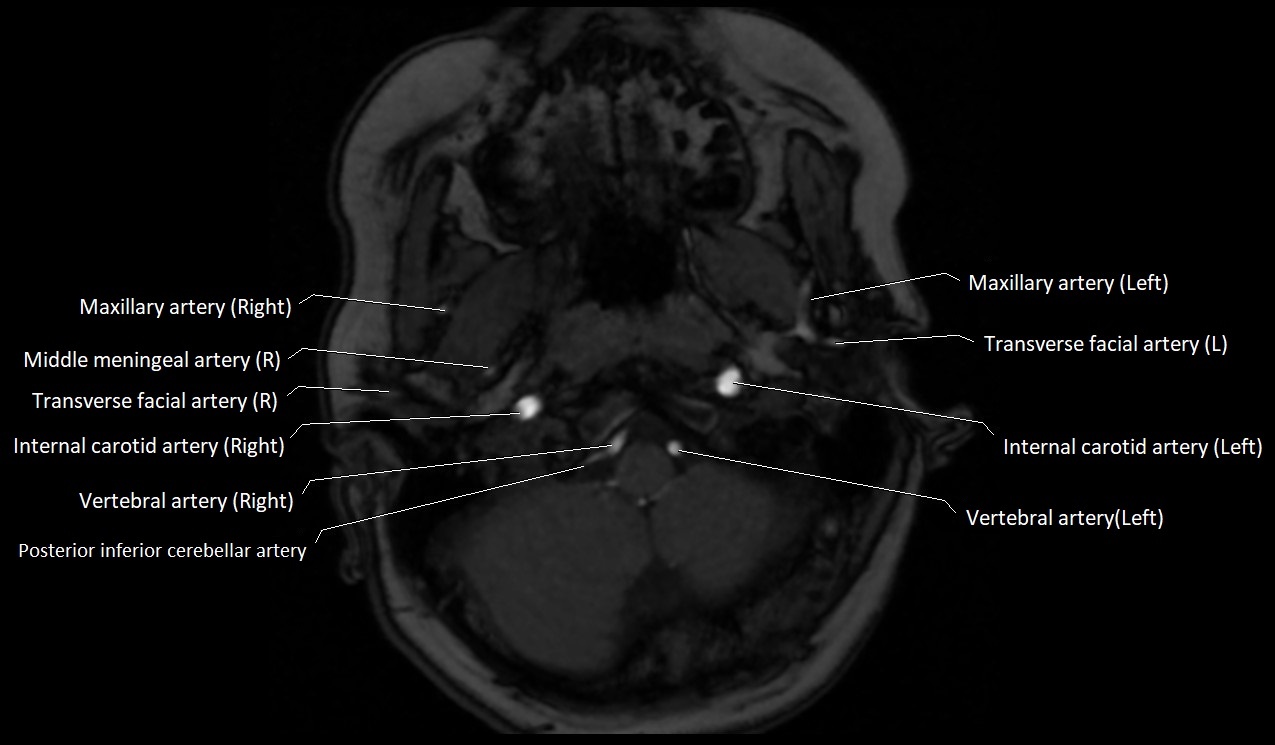

MRI Appearance:

• T1-Weighted Images:

• Appears as a tubular, hypointense (dark) structure relative to muscle

• May show flow void if the blood flow is fast

• T2-Weighted Images:

• Typically hypointense or isointense to muscle, but can be hyperintense if slow flow or stasis is present